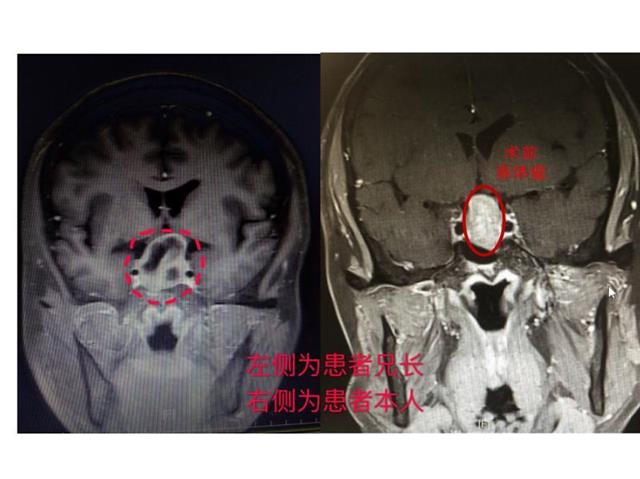

虽脑部警报再次被解除,但家族中接连查出脑瘤的情况引起了岑波的格外注意,经留心比对屈老和其六哥的影像资料,岑波惊讶的发现俩人的病变位置及性质都如出一辙,凭着高度的职业敏感和丰富的脑肿瘤诊治经验,他建议屈老的直系亲属最好进行脑部检查排除脑瘤的可能,必要的情况下可进行基因检测明确病因。此外,岑波提醒,双(多)胞胎中有脑瘤史或家族中有2名及以上脑瘤病患的家庭,其直系亲属最好提前做脑部检查,以尽早排除脑瘤的可能。